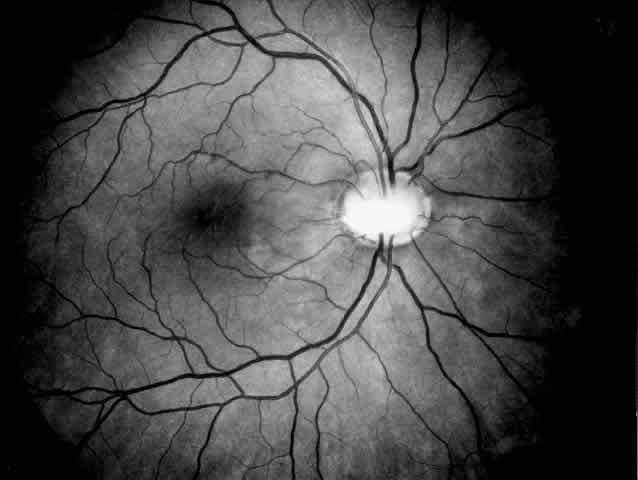

Alport's syndrome may affect the cornea, lens, and retina, the most characteristic ocular signs being posterior polymorphous dystrophy, anterior lenticonus, and superficial perimacular flecks (Fig. 4). There is growing evidence that the ocular abnormalities, like the glomerular lesions, result from a common defect in basement membrane formation.56,58,59 Changes are uncommon and subtle in young patients with Alport's syndrome and seem to increase in frequency and severity with age.60 The corneal changes associated with Alport's syndrome include endothelial vesicles compatible with posterior polymorphous dystrophy, subepithelial opacities,58 corneal arcus, and recurrent corneal epithelial erosions.

Fig. 4. Superficial perimacular flecks in a 15-year-old boy with normal vision. Alport's nephritis was diagnosed at the age of 3 years and progressed to end-stage renal disease at the age of 14 years. Perceptive high-tone hearing loss was detected at the age of 11 years. The proband's mother has had persistent microscopic hematuria since the age of 20 years but had no other manifestations of the disease.